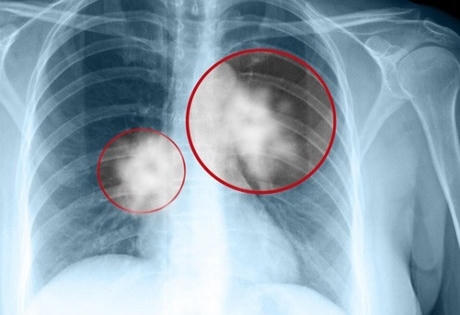

Ung thư phổi là một trong mười loại ung thư thường gặp và là nguyên nhân gây tử vong hàng đầu tại Việt Nam. Theo số liệu thống kê ở nước ta, trung bình một năm có khoảng 20.000 ca mắc ung thư phổi/năm.

Bệnh ung thư phổi có hai loại: Ung thư phổi tế bào nhỏ và ung thư phổi không tế bào nhỏ. Trong đó bệnh nhân mắc ung thư phổi tế bào nhỏ thời gian sống không kéo dài quá 6 tháng.

Bệnh ung thư phổi vô cùng nguy hiểm, có đến 70% người mắc bệnh ung thư phổi tử vong chỉ trong vòng 1 năm sau khi phát hiện.